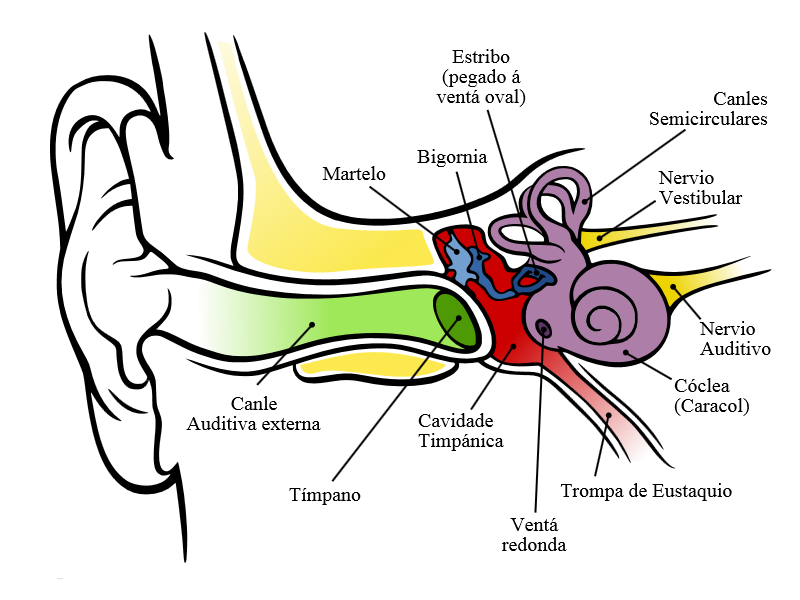

O oído humano está composto por 3 partes: oído externo, medio e interno.

- Oído externo: comeza no pavillón auricular, que conduce ao conduto auditivo externo o cal finaliza nunha membrana fina chamada tímpano.

- Oído medio: comunícase coa farinxe por medio das trompas de Eustaquio. A diferenza de presión entre ambos os dous oídos mantén tensado o tímpano. Aquí tamén se atopan 3 pequenos ósos chamados martelo, bigornia e estribo. Ao final está o conduto oval.

- Oído interno: existen dúas estruturas, o caracol, que é o encargado da audición, e as canles semicirculares, recheas dun líquido chamado endolinfa e que son as encargadas de manter o equilibrio.

O pavillón auditivo recibe o son e concéntrao polo conduto auditivo a través do tímpano cara ao oído medio.

Ao recibir as ondas sonoras, o tímpano vibra e este movemento transmítese aos tres ósos do oído medio que amplifican o son e o transmiten pola ventá oval ata o oído interno.

A vibración transmítese á endolinfa no interior do caracol, o cal move os cilios dunhas células que transforman a vibración do líquido en impulsos nerviosos, que se transportan ao nervio auditivo e de aí ao cerebro.

Estrutura do oído Modificado de commons.wikimedia.org |